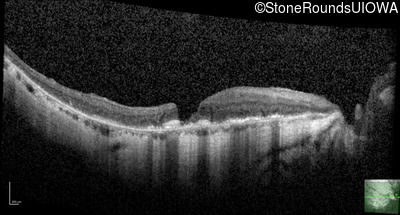

Optical Coherence Tomography - Right - 20/25 -1

Exemplar / OCT Stack